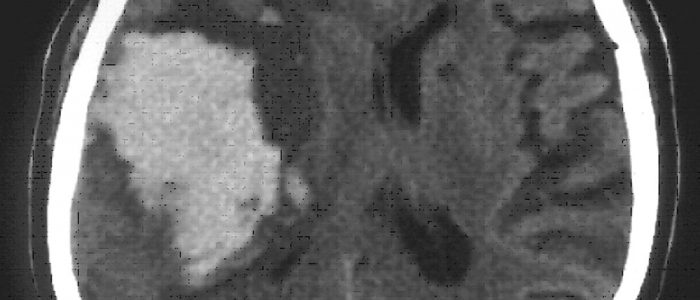

Во время диагностики ангиом следует проанализировать наличие симптомов, факторов и риска и уделить внимание семейной предрасположенности к онкозаболеваниям. Зачастую ангиома сосудов мозга — случайная находка во время компьютерной томографии (КТ). Этот метод неинвазивен, но не специфичен и значим только для опухоли большого размера.

Подтверждается диагноз гемангиомы мозга на основе аппаратного обследования – КТ или МРТ черепа.

МРТ (магнитно-резонансная томография) служит методом выбора для диагностики данной патологии, так как он гарантирует стопроцентную точность.